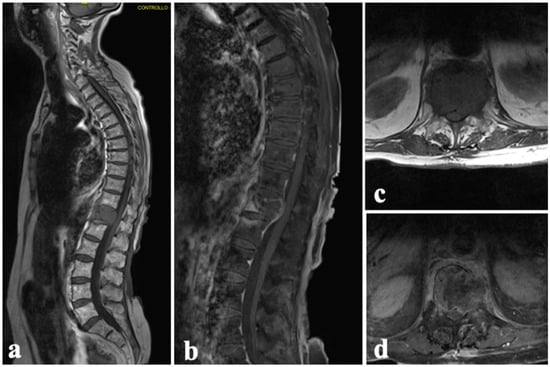

4. Case Series